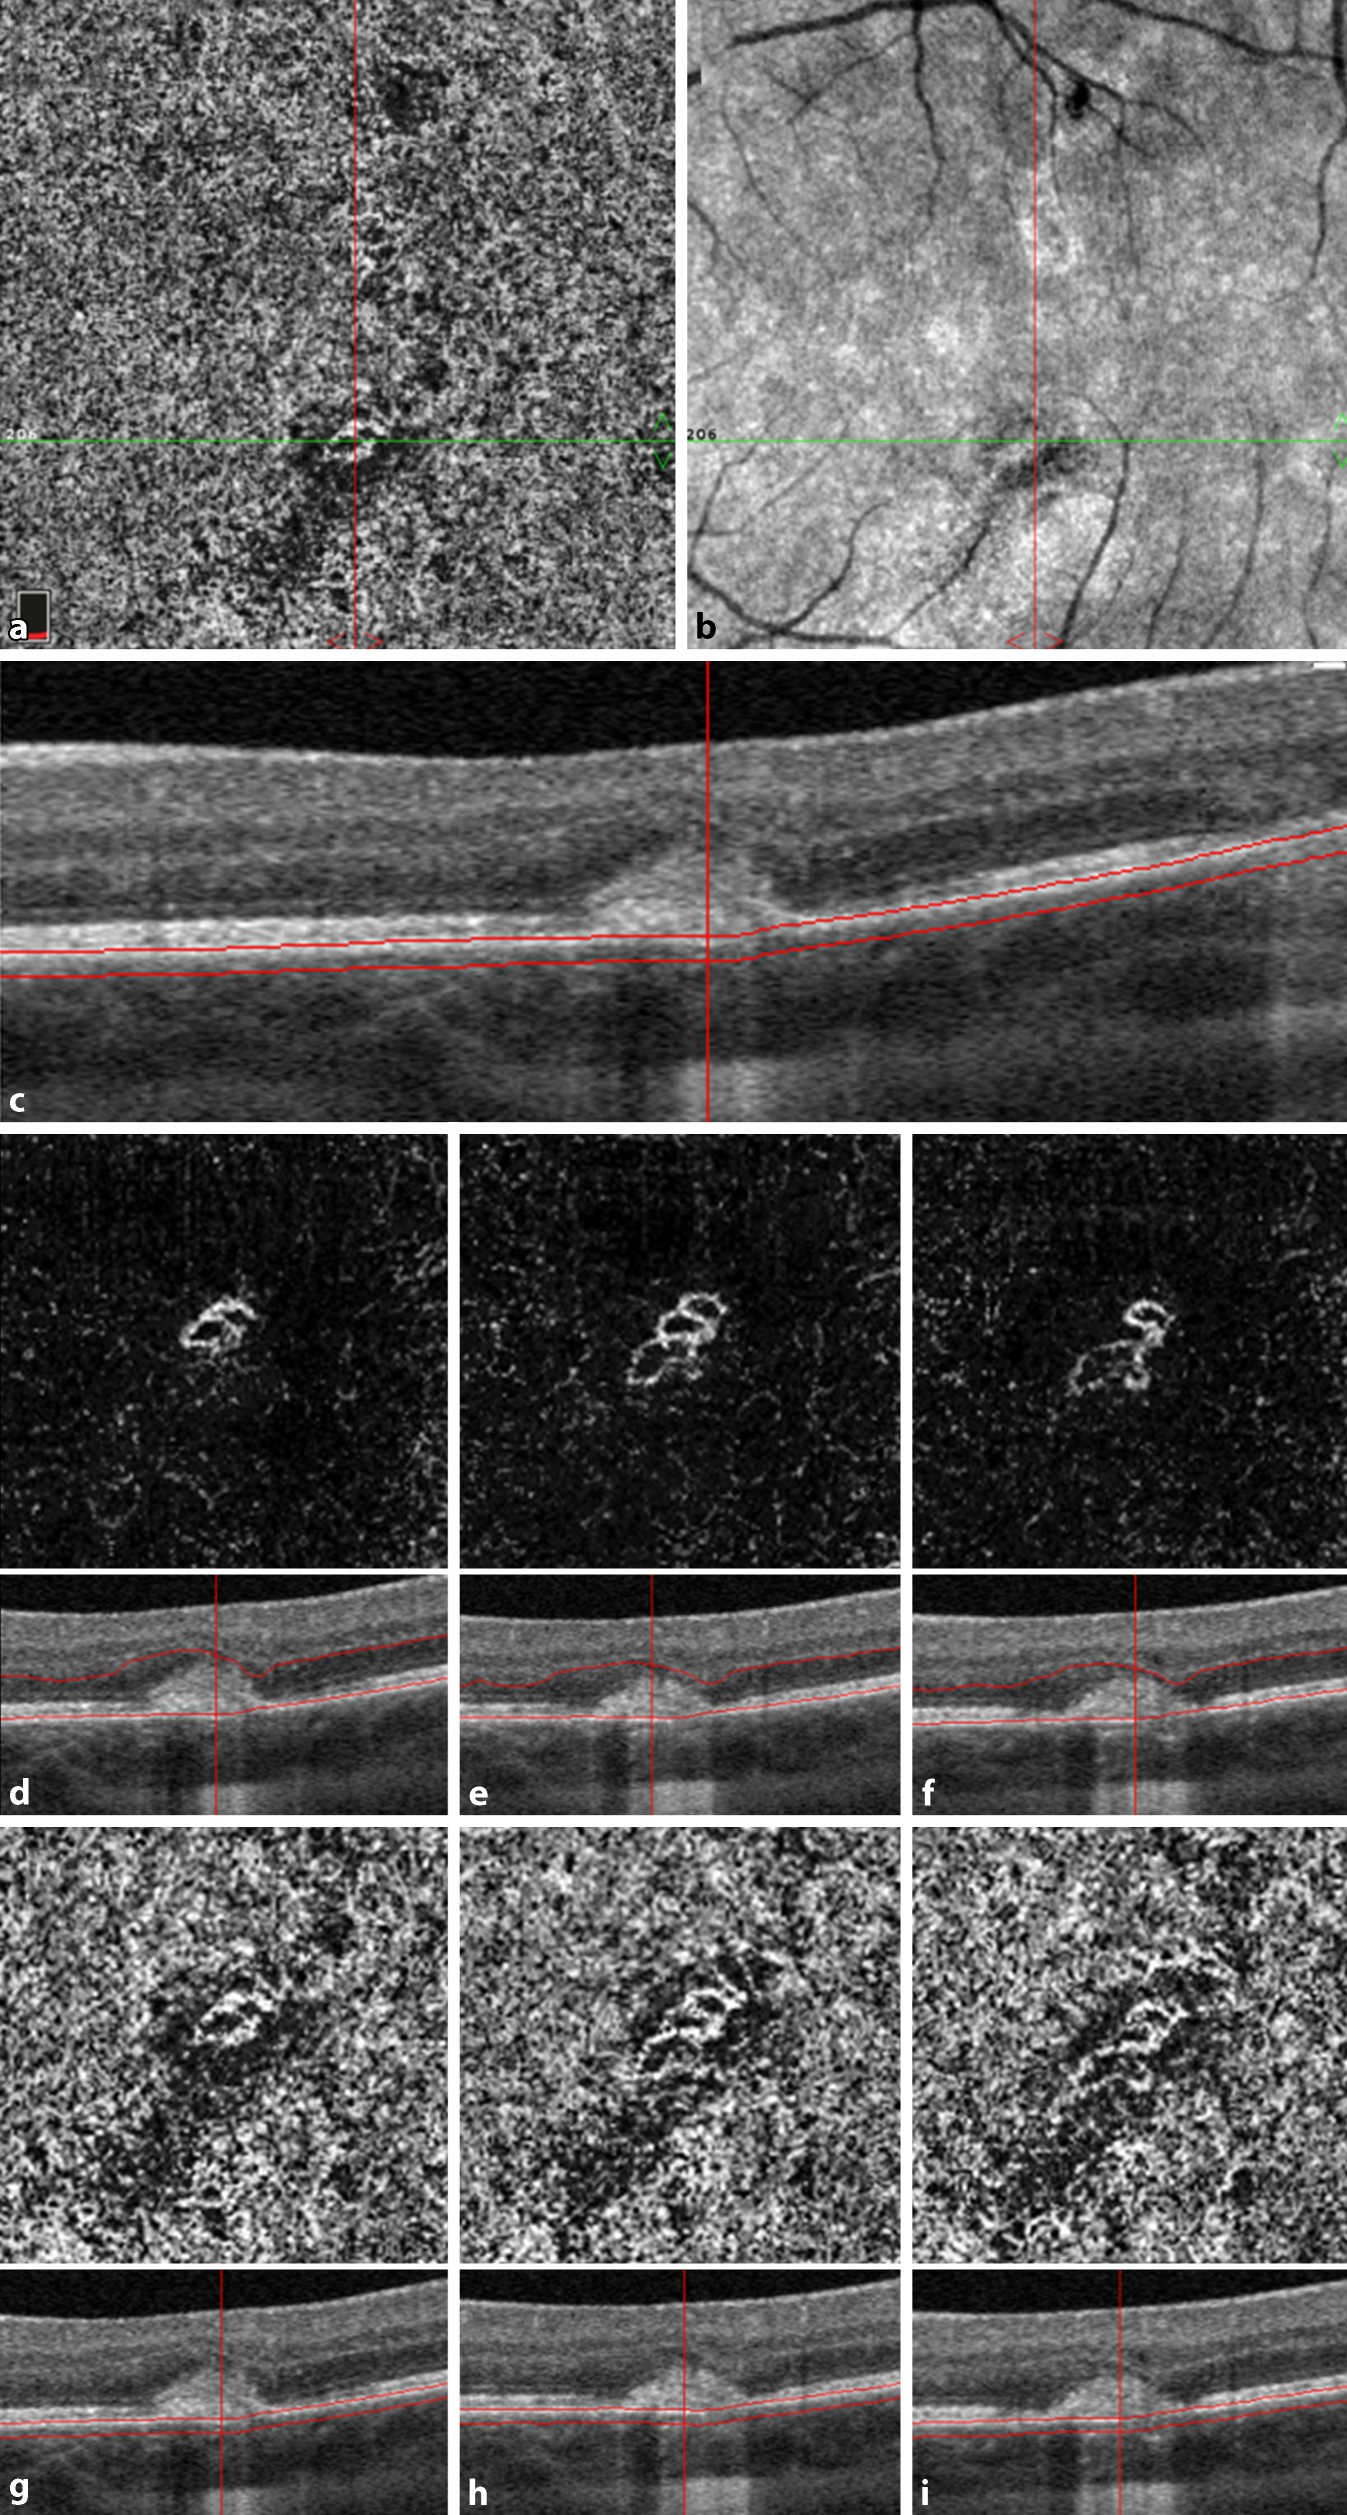

Abb. 6

Ausschnitte des makulären 3 × 3 mm optischen Kohärentomographie(OCT)-Angiogramms des linken Auges mit der umschriebenen choroidalen Neovaskularisation. a En-face-Angiogramm der Choriokapillaris, b Übersichtsinfrarotaufnahme, c korrespondierender Bereich in der spectral domain-OCT. d–i Morphologische Entwicklung im Zeitverlauf auf Höhe der äußeren Netzhaut (d–f) und der Choriokapillaris (g–i)

Bild vergrößern

Wir initiierten eine orale körpergewichtsadaptierte Kortikosteroidtherapie (Prednisolon 1 mg/kg Körpergewicht mit wochenweiser Reduktion über insgesamt 7 Wochen). Aufgrund fehlender Hinweise einer CNV-Aktivität wurde auf eine intravitreale Anti-vascular-endothelial-growth-factor(VEGF)-Therapie zunächst verzichtet. Eine Woche später zeigten sich die Läsionen umschriebener und regredient. Es bestand weiterhin kein Makulaödem bei stabilem Visus. Die anschließenden Kontrollen ergaben eine zunehmende Abgrenzbarkeit der chorioretinalen Herde mit fortschreitender Vernarbungstendenz bei insgesamt unveränderter Blutflussdetektion im Bereich der sekundären CNV (Abb. 6d–i).